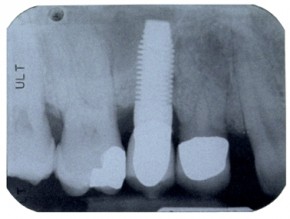

Impianti 2

Impianti e corone ceramo-metalliche nella zona dei molari inferiori, andati persi:

- per recuperare una adeguata masticazione in modo fisso sono stati inseriti due impianti endoossei,

- dopo tre mesi, sugli impianti convalidati dal test di stabilità, sono state posate due corone in ceramica su telaio metallico,

- dodici anni dopo la fine del trattamento: la radiografia di controllo mostra ancora la sempre perfetta osteointegrazione e funzionalità della cura,

- si può notare che rispetto alla radiografia di partenza, l'osso che nella zona del secondo molare presentava un difetto, stimolato dalla funzione masticatoria, sia ricresciuto e sia ancora totalmente integro.

Non vi è infiammazione nè patologia alcuna, la presenza degli impianti endoossei è, a detta del paziente, assolutamente impercepibile e comparabile alle radici naturali.